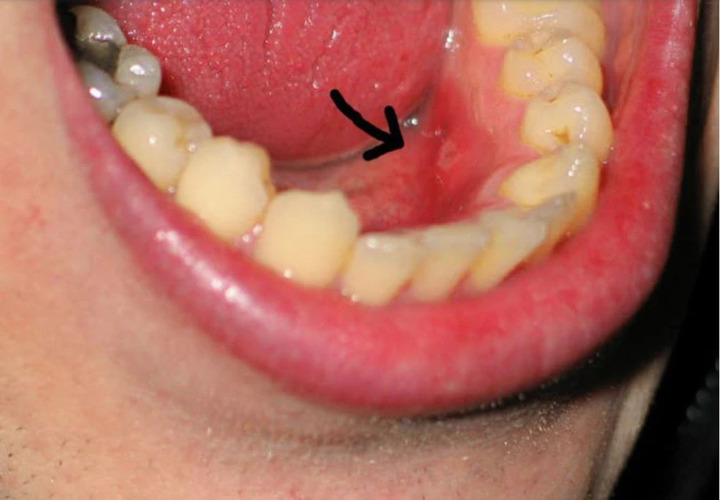

Ung thư khoang miệng: Dễ nhầm với nhiệt miệng

Theo bác sĩ Bệnh viện K, ung thư khoang miệng là bệnh ác tính có thể xuất hiện ở bất kỳ vị trí nào trong khoang miệng.

Ở giai đoạn sớm, ung thư khoang miệng thường không gây đau nhiều, thậm chí gần như không có biểu hiện rõ ràng. Người bệnh dễ bỏ qua vì các dấu hiệu rất giống với những vấn đề răng miệng thông thường.

Ung thư khoang miệng triệu chứng dễ nhầm với nhiệt miệng (Ảnh minh họa)

Một số triệu chứng dễ gặp nhưng dễ bị nhầm lẫn với nhiệt miệng gồm: Vết loét trong miệng kéo dài; mảng trắng hoặc đỏ bất thường trên niêm mạc miệng, lưỡi hoặc lợi; Đau âm ỉ hoặc rát nhẹ ở lưỡi, lợi, má trong; Chảy máu nhẹ không rõ nguyên nhân khi đánh răng hoặc ăn uống.

Khi bệnh tiến triển hơn, các dấu hiệu có thể rõ ràng hơn như: Khó nhai, khó nuốt, nói khó; Đau lan lên tai hoặc vùng hàm; Nổi hạch ở cổ; Sụt cân không rõ nguyên nhân.

Các bác sĩ lưu ý, điểm quan trọng nhất để phân biệt với bệnh lành tính là tính chất kéo dài và không đáp ứng với điều trị thông thường. Vì vậy, bất kỳ tổn thương nào trong khoang miệng tồn tại quá 2 - 3 tuần đều cần được kiểm tra chuyên khoa càng sớm càng tốt.